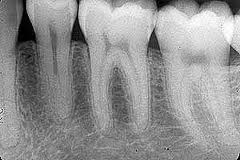

เป็นการ X – Ray เฉพาะซี่ฟันแต่ละซี่ โดยใช้ แผ่น sencor ขนาดเล็ก เพื่อตรวจความผิดปกติของฟันเป็นซี่ๆ ใช้ประกอบการตรวจหาฟันผุ หินปูน ความผิดปกติของกระดูกรอบรากฟัน เป็นต้น